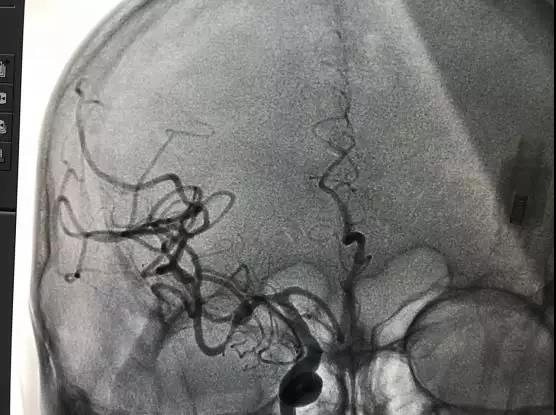

申请成为“卒中中心”和“综合防治卒中中心”的医院,也就成为衡量一家医疗机构卒中综合诊疗救治能力的最直接标准。“综合防治卒中中心”是卒中中心的高级形式,不仅要求医院能够进行急性脑血管疾病的常规治疗,还必须具备高难度的动静脉溶栓、桥接取栓及动脉瘤栓塞等综合救治能力,能够第一时间开通卒中中心转诊患者的绿色通道,医院的科研水平、人才培养也需要达到较高层次。

医院启动“三大中心建设”,正式成立卒中中心。以多学科协作模式为基础,打造了一支由神经内、外科专业力量,联动急诊科、120急救中心、检验科、影像科、药学科、康复科、介入室等多科协作的“脑卒中救治团队”,24小时联动待命。建立起包含急性期救治、早期康复、二级预防、随访宣教等功能于一体的相对独立的学科联合体系,实现了院前院内无缝对接,缩短了脑卒中患者入院检查、治疗的时间,有效降低了脑卒中患者的致残率和死亡率,实现了卒中救治的标准化。

伴随着地图的颁布,我区首例动脉取栓术成功独立完成,术后患者恢复良好。